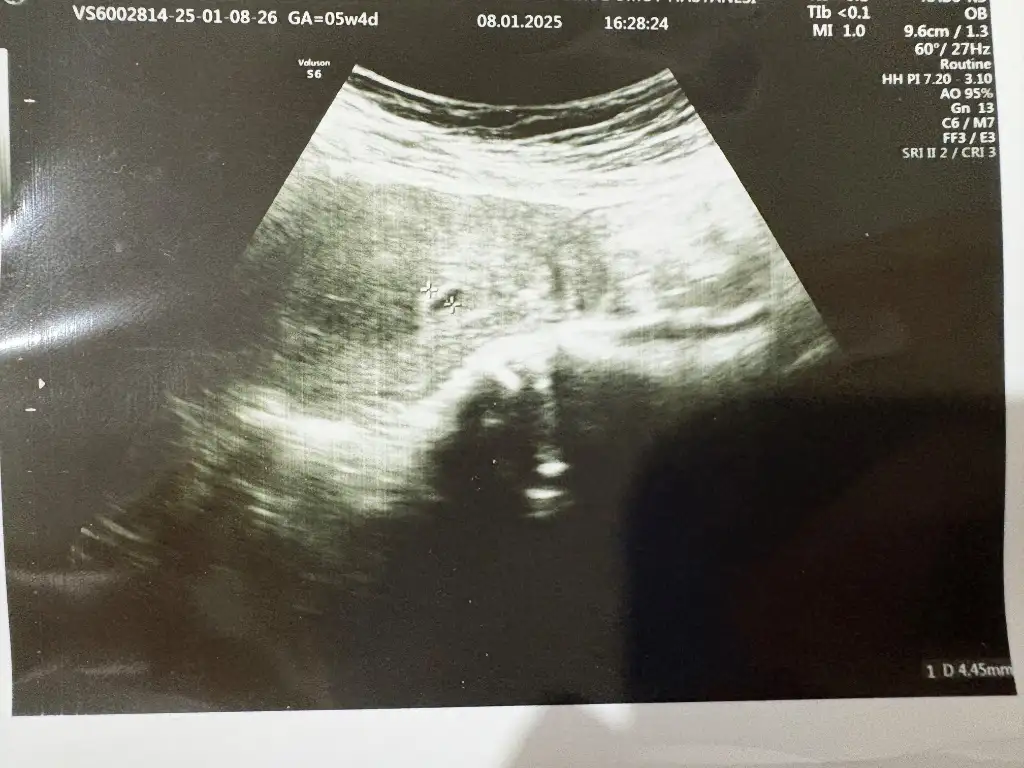

İnşallah sağlıkla kucağına alırsın canım bana da dua et en hayırlı zamanda hayırlı bir evladım daha olsunAynı durumu yaşıyoruz 3 kayıptan sonra tekrar pozitif gördüm umarım bu sefer tutunur

3 günde 4.75 kat artmış ki 2 günde en az 2 kat olması lazım diyorlar bence az değil ama tabii dr değilim :)Sat 15 Aralık 8 ocak 138 11 Ocak 656 çıktı az mı sizce

Ay inşallah sağlıklıdır valla çok gerginim kasıklarım da ağrıyınca çok korkuyorum3 günde 4.75 kat artmış ki 2 günde en az 2 kat olması lazım diyorlar bence az değil ama tabii dr değilim :)

Gayet güzel artmış canım hiç endişelenme iyidir o maşallahAy inşallah sağlıklıdır valla çok gerginim kasıklarım da ağrıyınca çok korkuyorum![]()